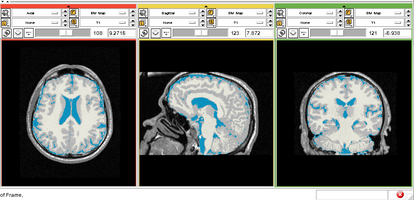

Physiological Brain Activity Longitudinal Study

- Collaborator: Laura Horky PI (Brigham and Women's Hospital(BWH)), Jon Hainer (BWH), Wendy Plesniak (BWH), Alexander Zaitsev (BWH), Ron Kikinis (BWH) and BWH Division of Nuclear Medicine

- Short description: Evaluate glycolitical brain activity in CSF and White Matter for the patients undergoing chemical therapy courses.

- Image specification: 1.5 Tesla ,Scanner: SIGNA EXCITE / GE MEDICAL SYSTEMS, T1, Axial Scans, TR/TI/TE=500/0/21 ms, pixel_xsize = 0.781251, pixel_ysize = 0.781244, fov = 0.000000, aspect = 7.679990, thick = 5.000000, space = 1.000000

- Used Task: MRI Human Brain Hemisphere